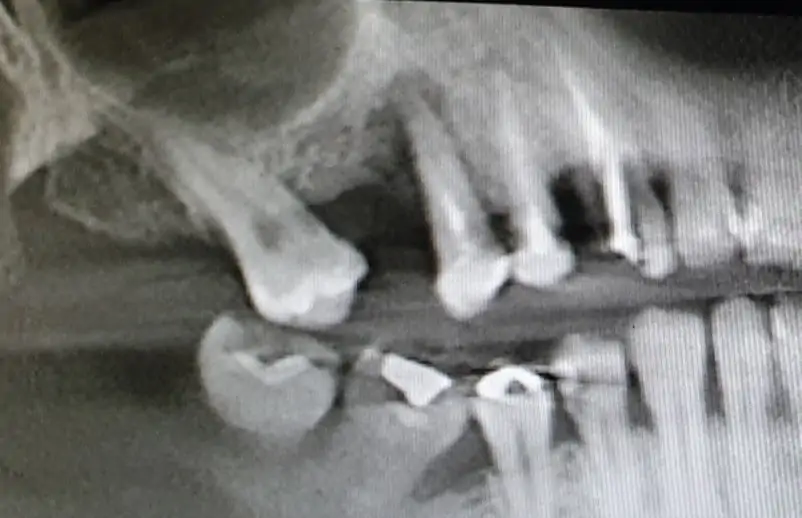

From the first radiographic examination (OPT and CT scan) there is an evident periapical granuloma and pain with pressure on 14 and 15, while 17 element is parodontopathic, moreover there is a lack of bone in 16 and 17 area with chronic infections at the level of the maxillary sinus. Due to the clinical history of the patient it was not advisable to go for a sinus lift, it has been planned the insertion of a pterygo implant and 2 post extractive EV implants. During the surgery, biomaterial (Novocor from B&B Dental) was added to the insertion of the implants  to remodel the ridge horizontally, given the evident bone deiescence. Two temporary provisional titanium abutments were then inserted, welded with a two titanium bar. We inserted 2 EV implants to reach a better primary stability. As the patient is bruxist the crowns have been totally unloaded. The pterygoid implant will be loaded on a second session.